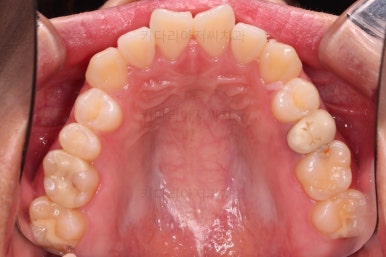

1. 처음 내원 시의 입안의 모습

부산치아교정잘하는곳 키다리아저씨치과에 처음 내원하셨을 당시의 입안 모습입니다.

얼핏 보면 많이 삐뚤어지지는 않은 편인데, 눈에 바로 띄는 앞니가 뻗쳐 있으면서 획 돌아있는데요. 정렬이 필요한 상황이었습니다.

어금니쪽은 많이 삐뚠 편은 아니었으며, 윗니 앞니가 많이 앞으로 뻗쳐 있는 상태였습니다.

이런 뻗침이 왜 생겼는지는 아래에서 다시 한 번 말씀 드릴게요.

아까 말씀 드렸던, 왜 윗니 앞니만 뻗칠까?에 대한 대답은 "주걱턱의 골격구조를 가지셔서" 입니다.

아래턱이 앞으로 나오면 나올수록 윗니는 앞에 있는 아래턱과 만나기 위해 앞으로 뻗치는거죠.